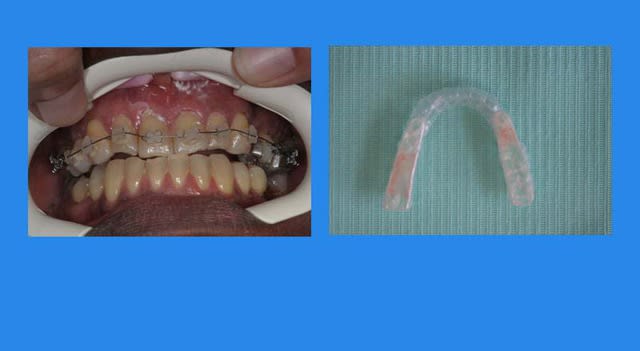

Pose d’un Q.H. à forces asymétriques

3 s1as6b - Eugenol

associé a un arc Sup. 0.014 thermique et a une gouttière de surélévation

4 qnsxnr - Eugenol